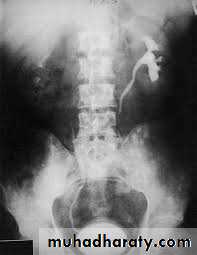

High density renal stonesStage horn calculus KUB filmsradio opaque stones